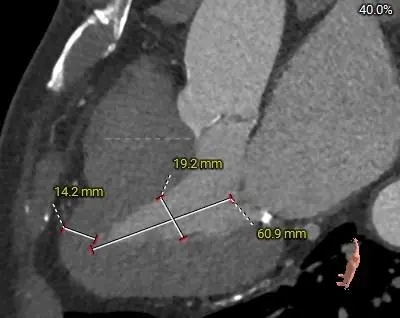

主动脉根部测量

ANNULUS

周长径23.7

周长径24.2

34.9mm&32.1mm&34.3mm

周长径31.2

周长径41.7

瓣上结构测量

周长径26.9

周长径25.2

冠脉风险评估

Left Coronary 8.0mm

Right Coronary 18.7mm

Left Ventricular

左冠开口较低,结合瓦氏窦大小,预估冠脉风险相对较低

外周入路评估

-

血管轻微迂曲

腹主、弓部可见钙化斑块

血管内径充足

主动脉弓平缓

66°横位心

右侧股动脉主入路,超硬导丝支撑下植入大鞘,左侧辅入路

冠脉风险不高,不进行提前保护,球囊预扩及瓣膜释放过程中评估冠脉灌注情况

建议20mm球囊预扩,患者小心室,小球囊扩张降低循环崩溃风险

使用ScienCrown™全可回收主动脉瓣膜系统植入TF27号瓣膜